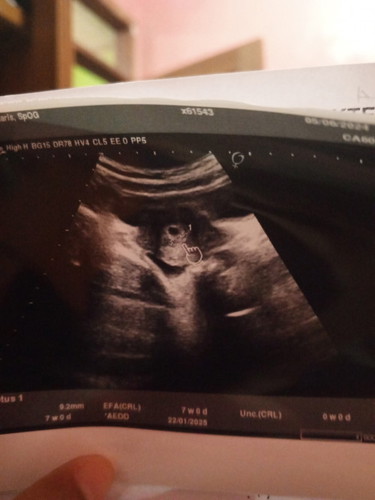

Keluar gumpalan darah hamil 7week

Bun ada yang sama ga kaya aku, sore tadi waktu jam 3 keluar gumpalan darah dibarengi keram . Aku langsung usg ke dokter obgyn. Udah berpikiran gugur, tapi kata dokter masih ada kantungnya dan bilang gapapa cuma harus bedrest total. Tapi sekarang masih kepikiran soalnya di gumpalan darah ada kaya jaringan gitu, ga sempet aku foto keburu lemes panik 🥲 #SeriusTanya #Sharing_dong_Bund